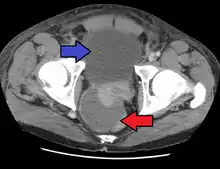

Acute prostatitis is relatively easy to diagnose due to its symptoms that suggest infection. The organism may be found in blood or urine, and sometimes in both.[2] Common bacteria are Escherichia coli, Klebsiella, Proteus, Pseudomonas, Enterobacter, Enterococcus, Serratia, and Staphylococcus aureus. This can be a medical emergency in some patients and hospitalization with intravenous antibiotics may be required. A complete blood count reveals increased white blood cells. Sepsis from prostatitis is very rare, but may occur in immunocompromised patients; high fever and malaise generally prompt blood cultures, which are often positive in sepsis. A prostate massage should never be done in a patient with suspected acute prostatitis, since it may induce sepsis. Since bacteria causing the prostatitis is easily recoverable from the urine, prostate massage is not required to make the diagnosis. Rectal palpation usually reveals an enlarged, exquisitely tender, swollen prostate gland, which is firm, warm, and, occasionally, irregular to the touch. C-reactive protein is elevated in most cases.[4]

Severely ill patients may need hospitalization, while nontoxic patients can be treated at home with bed rest, analgesics, stool softeners, and hydration. Men with acute prostatitis complicated by urinary retention are best managed with a suprapubic catheter or intermittent catheterization. Lack of clinical response to antibiotics should raise the suspicion of an abscess and prompt an imaging study such as a transrectal ultrasound (TRUS).[7]